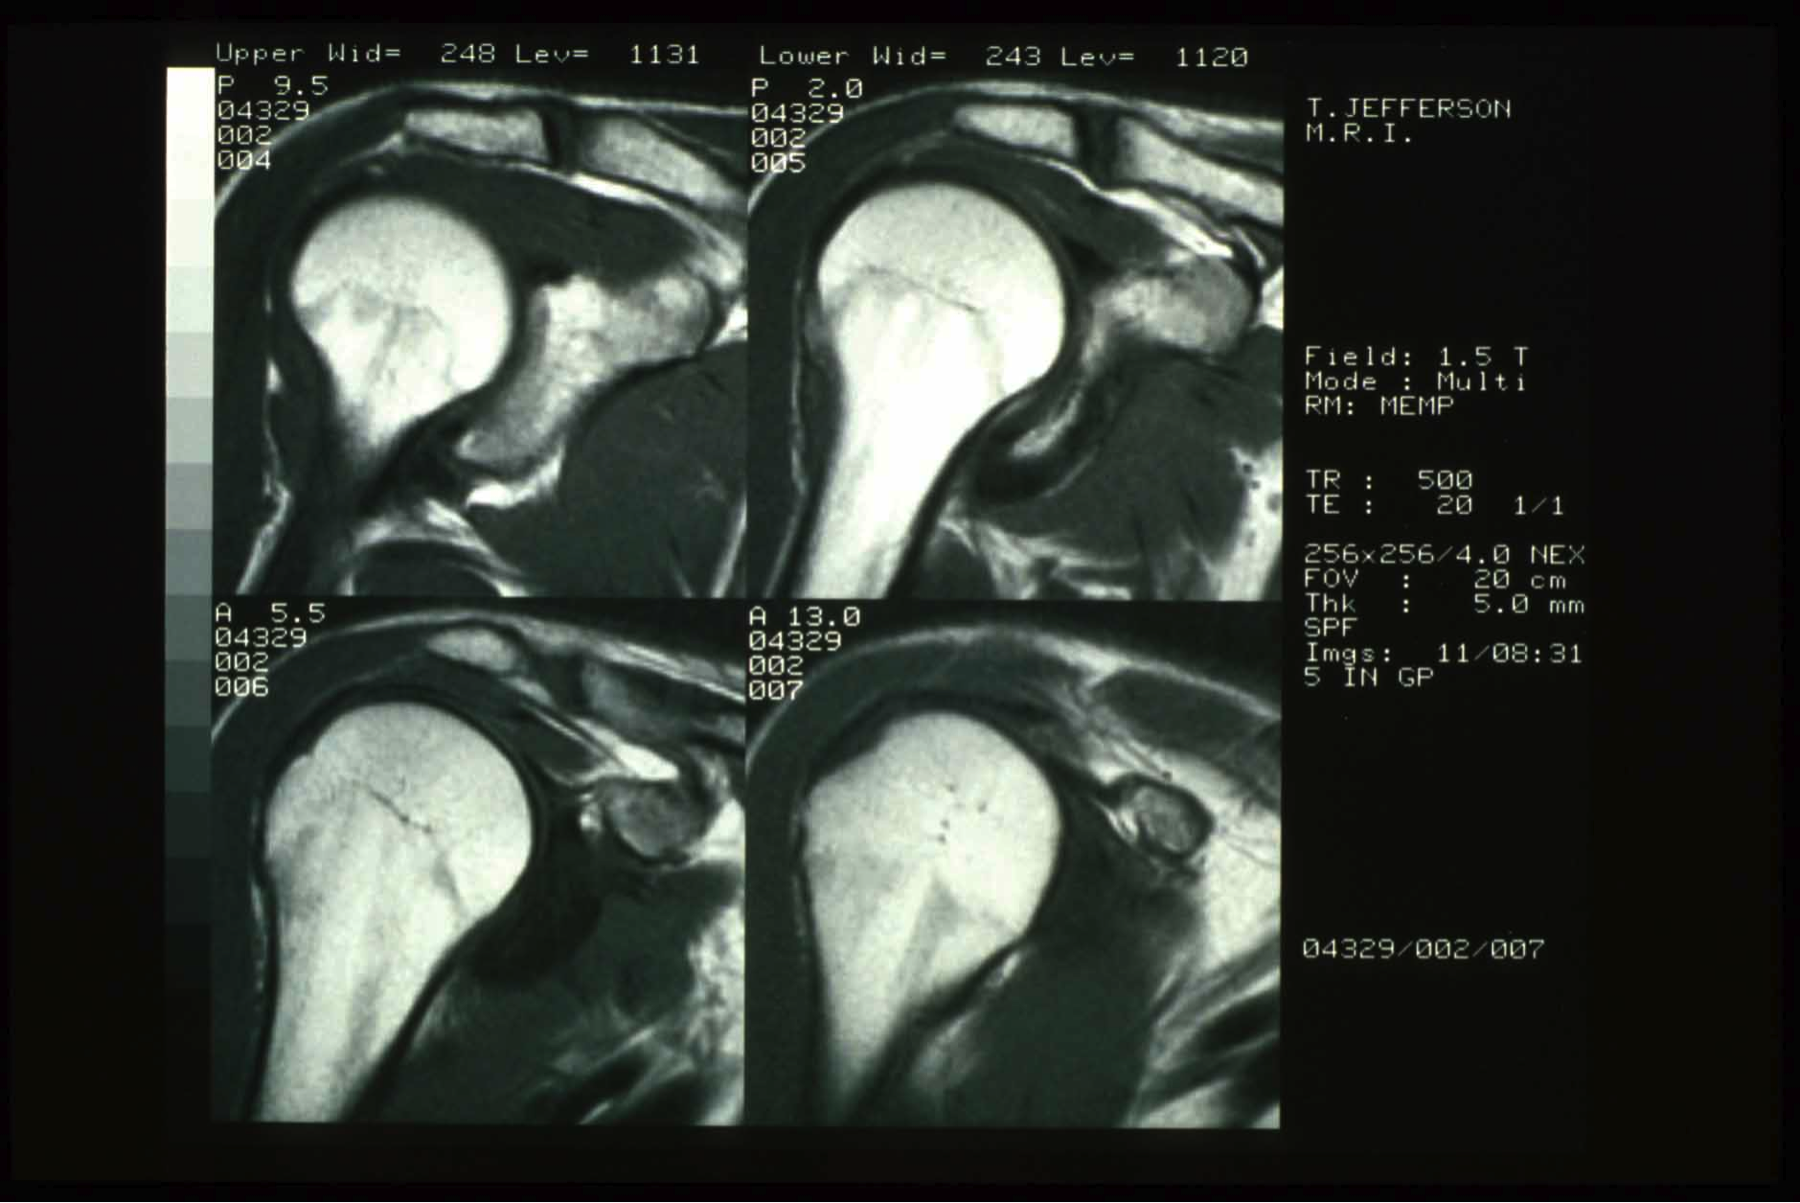

suffering-for-science-shoulder